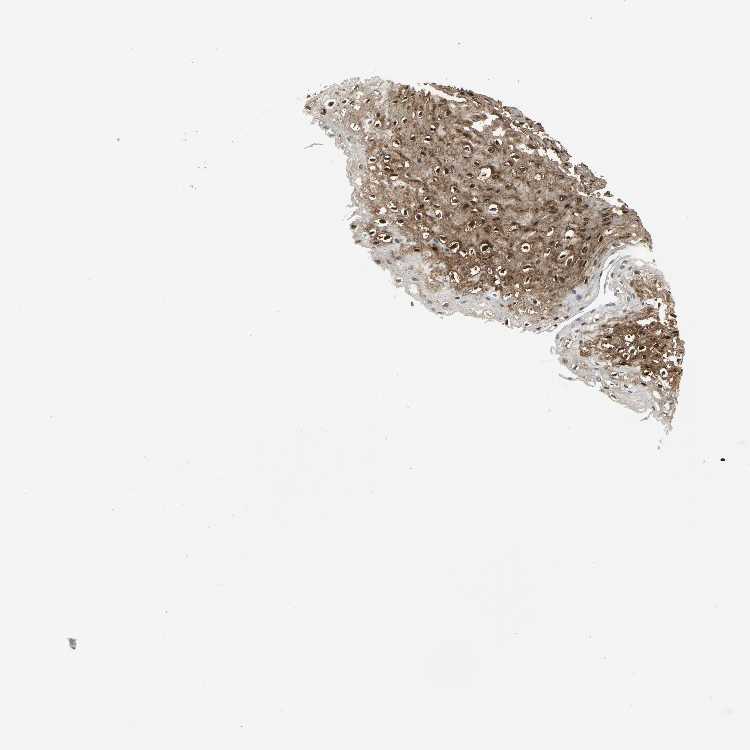

ESOPHAGUS - Antibody stainingi

Antibody staining in the annotated cell types in the current human tissue is reported as not detected, low, medium, or high, based on conventional immunohistochemistry profiling in selected tissues. This score is based on the combination of the staining intensity and fraction of stained cells.

Each image is clickable and will lead to virtual microscopy that enables deeper exploration of all samples and also displays staining intensity scores, fraction scores and subcellular localization as well as patient and tissue information for each sample.

Antibody HPA011105Antibody CAB006268Antibody CAB040552

Squamous epithelial cells HighHighHigh